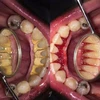

تسوس الأسنان

نزيف اللثة

اعوجاج الأسنان

أمراض الأسنان واللثة